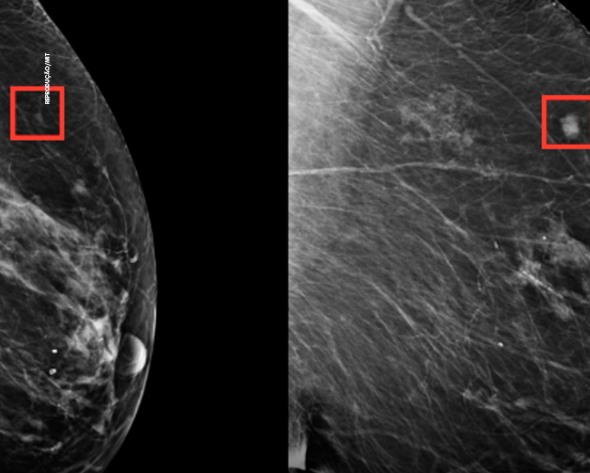

Desenvolvida pelo Massachusetts Institute of Technology (MIT), a tecnologia analisa exames de mamografia e estima a probabilidade de desenvolvimento da doença em até cinco anos. O modelo já havia sido adaptado à realidade local pelas instituições envolvidas, com resultados publicados em periódico científico.

Durante o estudo, todas as mamografias serão avaliadas pela IA. Pacientes classificadas com maior risco serão encaminhadas para exames complementares, como ressonância magnética, enquanto o grupo de controle seguirá o protocolo tradicional. A comparação entre os grupos deve medir a capacidade da ferramenta em ampliar a detecção precoce de tumores.